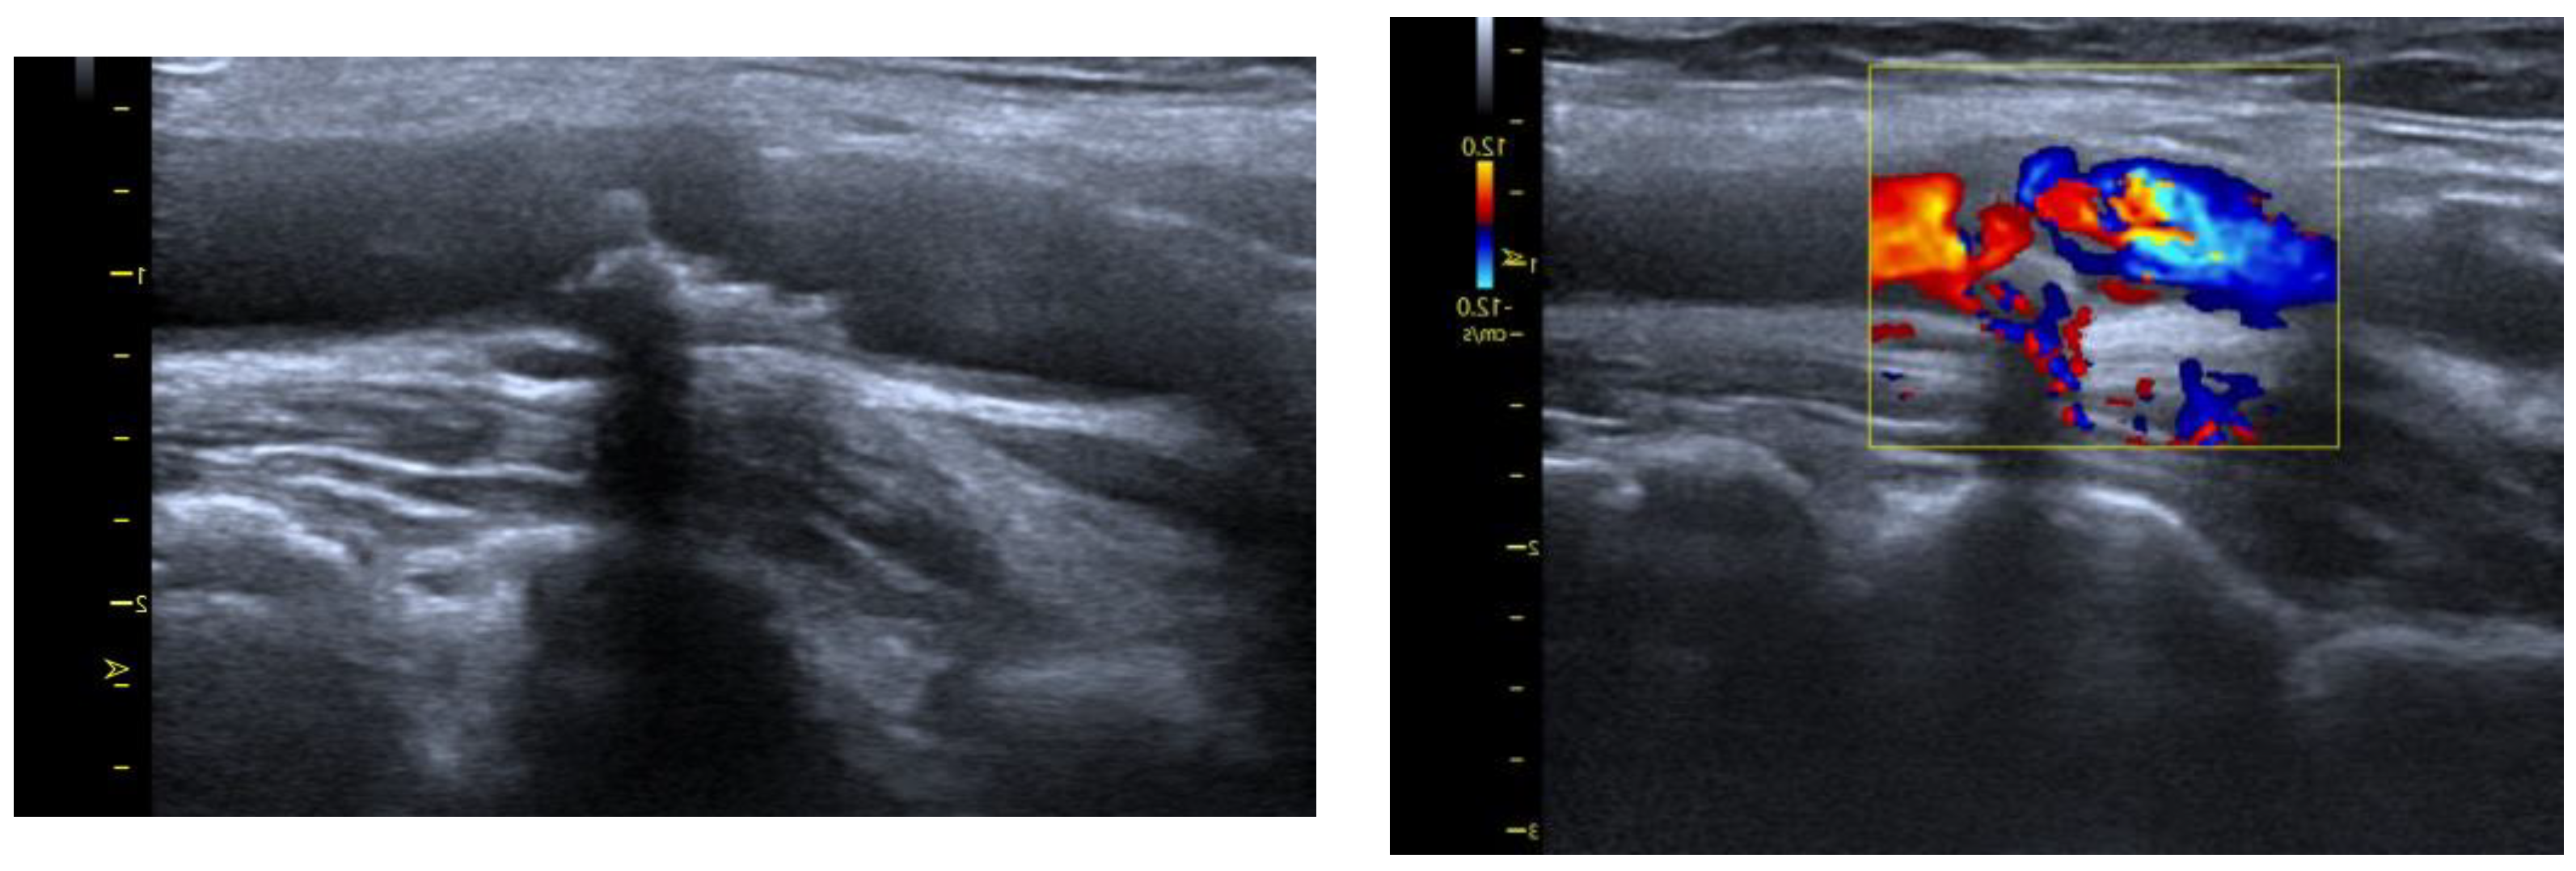

4.2. Arteriosclerotic Plaque Examination

The examination of the carotid arteries and assessment of complex intima media thickness (C-IMT) in the extracranial segment was performed using B-mode ultrasound with a linear probe at a frequency of 7.5–10 MHz. According to the Atherosclerosis Risk in Communities Study (ARIC) [95], the C-IMT was evaluated 3 times, and the mean score was taken into consideration. The measurement was performed in the distal common carotid (1 cm proximal to the carotid bulb). For confirmation of atherosclerotic plaque in the carotid artery, we assumed the thickness of the C-IMT complex was >1.5 mm or the presence of plaque, in accordance with the guidelines (Figure 3). We decided to use Carotid MRI to look at the structure of atherosclerotic lesions when there were signs of ruptured plaques, such as fibrofatty; intraplaque hemorrhagic; echolucent appearance; irregular surface.

Figure 3.

Ultrasound protocol.